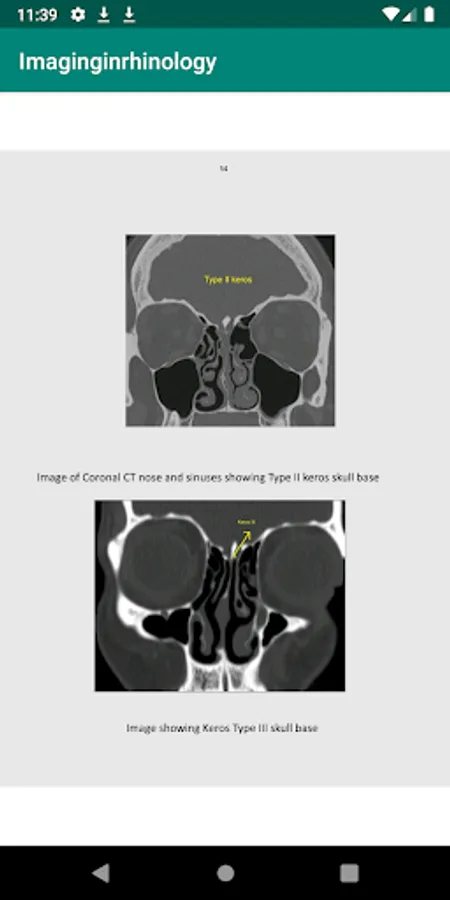

Imaging plays a vital role in the diagnosis of conditions involving nose and sinuses. It also serves as a road map to the surgeon during various surgical procedures involving nose and sinuses. Intranasal anatomy is highly variable. Without the road map provided by imaging a surgeon will be lost.

This app describes the imaging process in detail. It will help the students and practitioners of otolaryngology to fine tune their ability to study these images. There are more than 300 CT images with detailed description. These images are from the image collections of the author. This app will also serve as an atlas of imaging in rhinology.